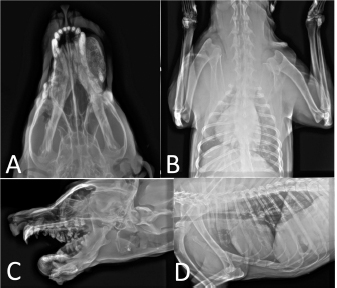

The skull radiographs were performed in dorsoventral and lateral projection which showed the intense and well-demarcated edge with a short transitional zone between normal and abnormal bone. There was a smooth rounded radiopaque appearance rostral of bilateral mandibles. The right mass size measured 8 × 4 cm and prevent normal chewing. The left mass has no remarkable changes in radiology in comparison to the left mass. The periosteal reaction and invasion of the surrounding soft tissue were not seen. Thoracic radiographs did not indicate pulmonary metastasis (Fig. 2).

Fig. 2. (A and C) Thoracic radiographs which are depicted there was no metastasis to the lungs. (B and D) The radiographs from the mandibular mass was performed.